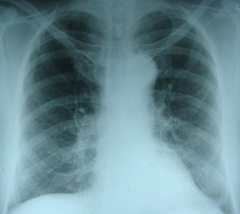

По мере того, как приступ развивается, при прослушивании легких определяются влажные разнокалиберные хрипы над различными участками легких, дыхание в этих участках либо ослаблено, либо вовсе отсутствует. Если во время приступа провести рентгенологическое исследование характерными симптомами отека легких будут их расширенные корни, очаговые крупные тени с нечеткими контурами (при этом прозрачность легочных полей понижена).